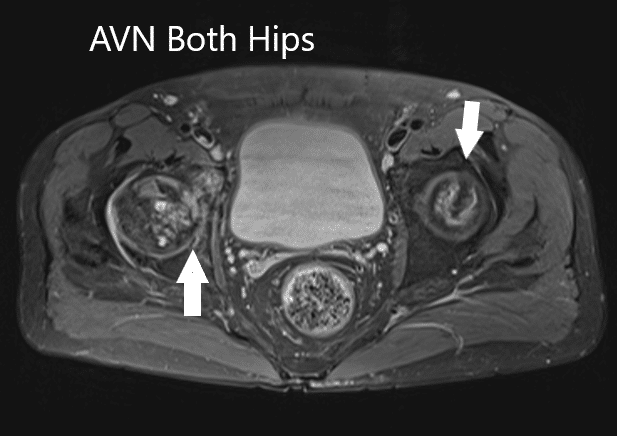

MRI suggested marked signal attenuation of bilateral femoral heads. There was a collapse of the right head and precollapse stage 2a of the left hip.

Axial section T2WI showing bilateral AVN of the femoral heads